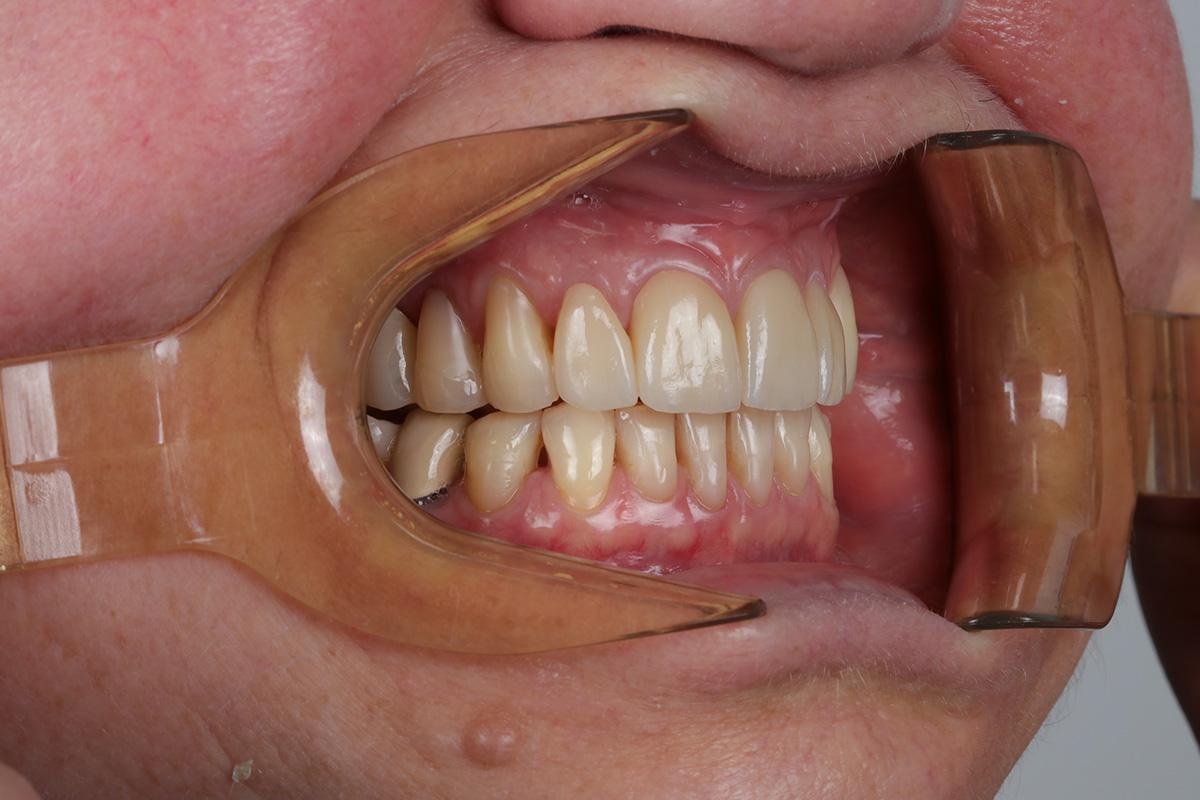

Pod kierownictwem lek. stom. Michała Badowskiego po wnikliwej analizie została przeprowadzona korekta dziąseł i pozbycie się nieestetycznych koron na podbudowie metalowej, eliminując tym samym nawracające stany zapalne dziąseł.

Następnie została wykonana wizualizacja nowego uśmiechu, idealnie dopasowana do twarzy Pacjentki. Po jej akceptacji, przygotowaliśmy komplet koron i licówek pełnoceramicznych na górne i dolne zęby.

Całe leczenie trwało zaledwie 3 miesiące!

Dzięki współpracy lek. stom. Michała Badowskiego i techn. dent. Joanny Gancarz z laboratorium Dentalscan Pacjentka zachwyca pięknym uśmiechem!